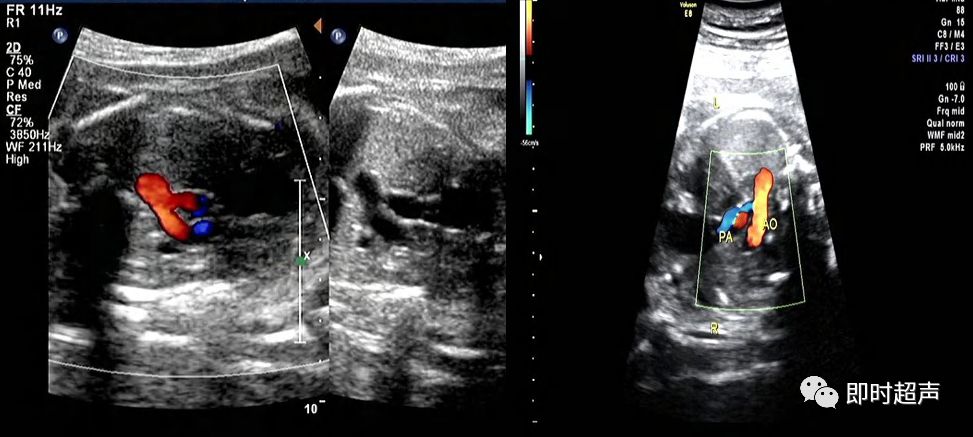

肺动脉增粗、主动脉正常

肺动脉瓣缺如症